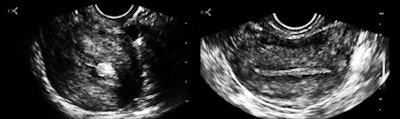

Vaginal bleeding seemed to be a pretty common presenting complaint, and even the first few cases included examples of the range of causes separable by ultrasound: polyps (figure 5a), endometrial hyperplasia, and adenomyosis.

The polyp case was a woman with a three-year history and no diagnosis. The adenomyosis patient had heavier bleeding for almost the same length of time and was deathly pale when she presented during a clinic "ultrasound day"; anemia did not seem to have been a clinical consideration. The endometrium was reduced to a thin, denuded basal layer in another woman with a month of bloody flow (figure 5b).

I am including this case because it reminded me of a clinical pearl: Whenever you have vaginal bleeding without an ultrasonically visible cause, think of clotting disorders such as von Willebrand disease.